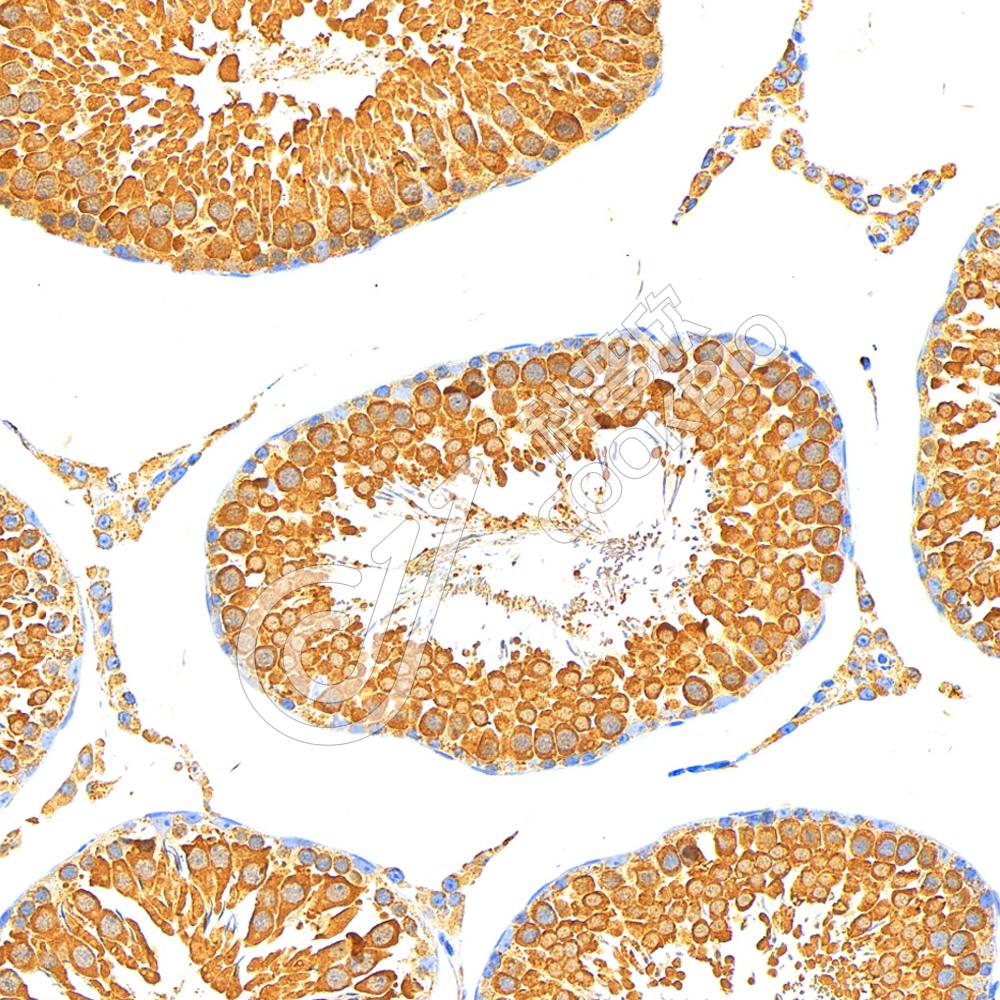

IHC检测GRP78 BiP蛋白(货号 K545294).

样品: 大鼠睾丸, 4%多聚甲醛 (货号KSG1101) 固定12-24小时.

抗原修复: 柠檬酸抗原修复液(干粉, pH 6.0) (KSG1201), 高压锅均匀喷气计时2分钟.

—抗: 1: 1300稀释, 4℃ 孵育过夜.

二抗: S-vision免疫组化多聚二抗(山羊抗小鼠), 即用型(货号KB3903), 室温孵育20分钟.